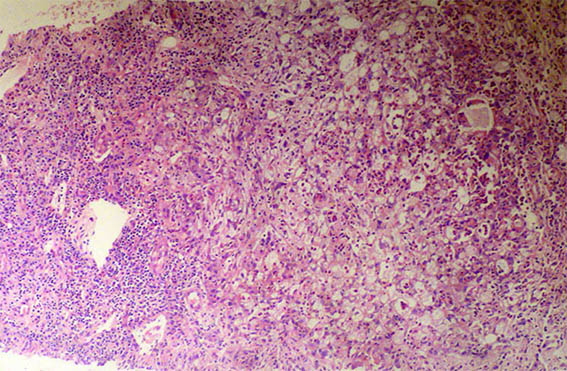

Figura 1. H&E, X100.